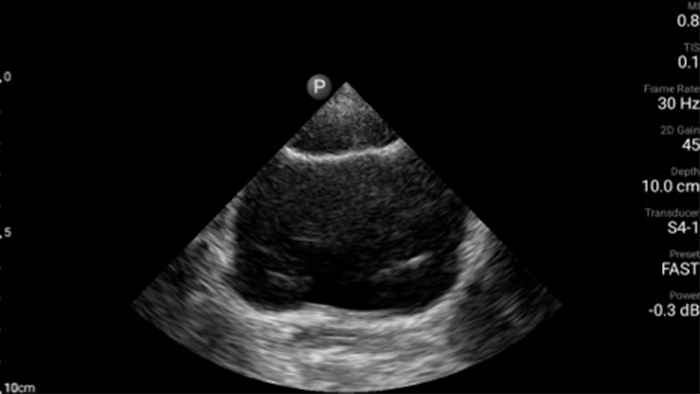

Use Lumify for airway and pulmonary assessment

Lumify POCUS solutions can help you detect the endotracheal tube within the trachea, assist in emergent cricothyrotomy procedures, diagnose pleural effusion and interstitial alveolar diseases.

Case study

A patient with dyspnea

Pre-hospital point of care cardiac ultrasound: pulmonary embolism